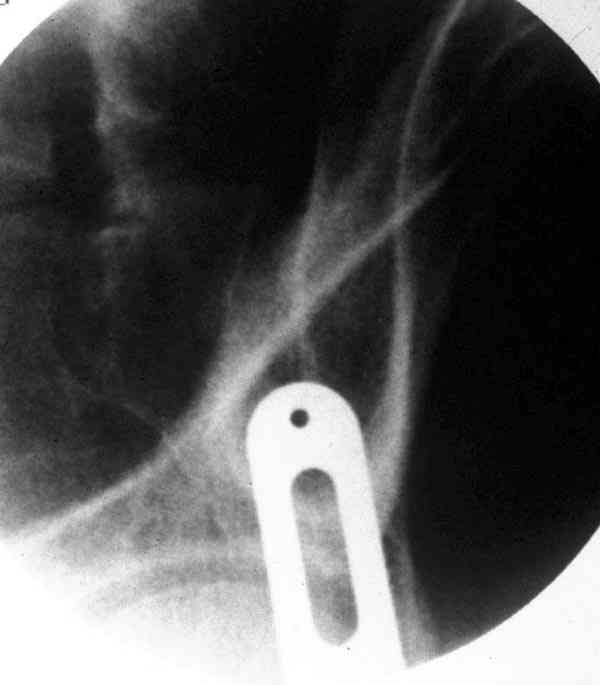

При свежем случае показана фиксация передней колонны к задней (снимки), компрессирующим винтом минимальным перкутанным методом по супраацетабулярной линии и в зависимости от состояния КПС.

iliac view

obturator tear drop view

obturator view

column model

Поэтому, в ранних и в спорных сомнительных случаях полезно проведение EUA (evaluation under anesthesia) в условиях операционной с доказательными нагрузочными рентгеновскими снимками. В данном случае, учитывая молодой возраст и прошедшее время, я бы оставил больного для дальнейшего консервативного наблюдения.

Стандартные снимки ацетабулума по Judet и снимки таза (инлет и оутлет) подскажут дальнейшую тактику по нагрузке.